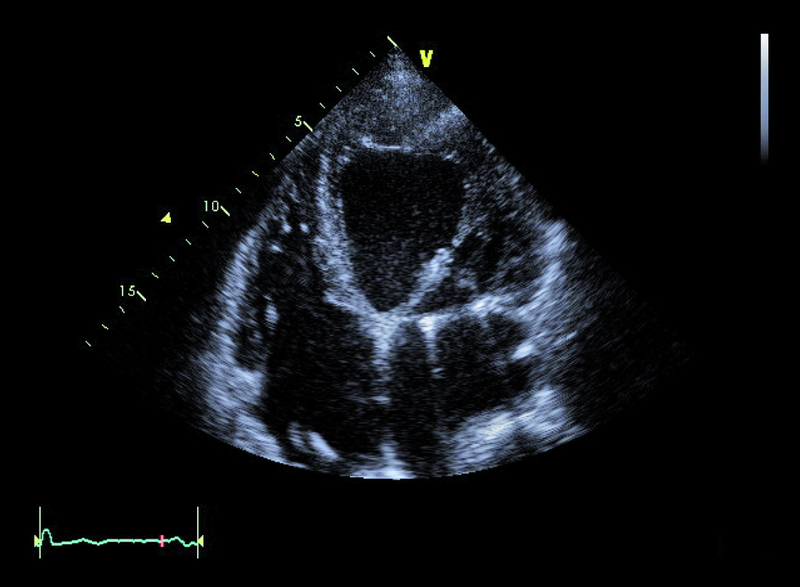

Mężczyzna, lat 68. Jakie patologie można rozpoznać na rycinach?

1. Powiększenie jamy lewej komory (ryc. 1).